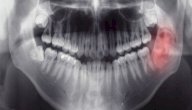

هو عبارة عن نموّ سرطاني يُصيب أي جزء من الفم مثل سطح اللسان أو الجزء الداخلي من الخدين أو سقف الفم أو الشفتين أو اللثة، وكما يمكن أن ينمو أيضًا في أجزاء أقل شيوعًا مثل الغدد اللعابية واللوزتين والبلعوم، ويُعدّ سرطان الفم سادس أكثر أنواع السرطان شيوعًا في العالم، وغالبًا ما يُصيب الأشخاص الذين تزيد أعمارهم عن 55 عامًا، وهو أقل شيوعًا في الأشخاص الذين تقل أعمارهم عن 50 عامًا، كما إنه أكثر شيوعًا في الرجال عن النساء، وسيناقش هذا المقال طرق تشخيص سرطان الفم.[١]

• الأشعة: قد يطلب الطبيب إجراء مجموعة متنوعة من الأشعة لتحديد ما إذا كان السرطان قد انتشر خارج الفم، بما في ذلك الأشعة السينية والأشعة المقطعية وأشعة الرنين المغناطيسي والتصوير المقطعي بالإصدار البوزيتروني وغيرها.